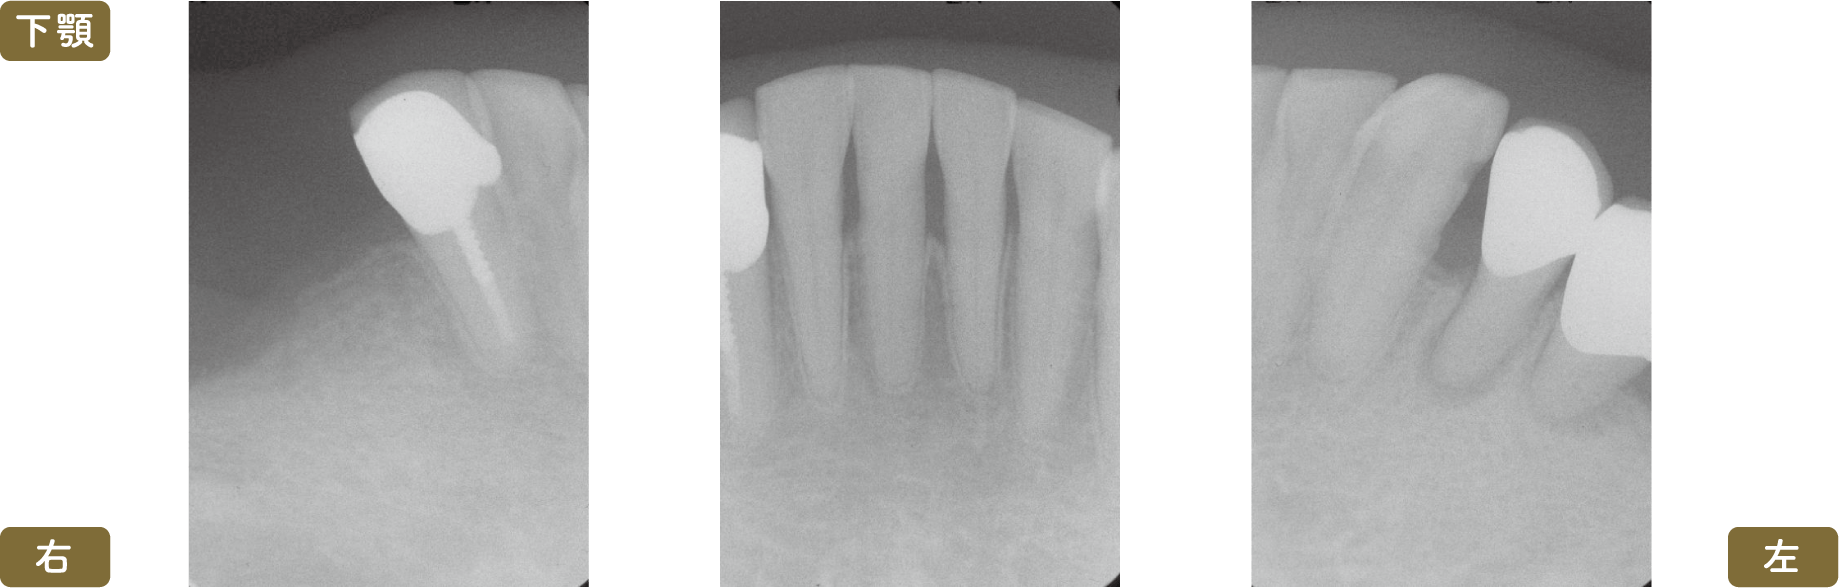

■術前レントゲン写真

左下4,5番の歯は根管治療をおこなう必要がありますが、すでに動揺がみられることと義歯を支える歯という点から、積極的な介入は行わず義歯を再製するのみという治療方針となりました

動揺はありますが、このスイングロックアタッチメントを使用することにより動揺歯が二次固定されて動きが少なくなります

上顎は総義歯のため、下顎のみのレントゲン写真です

レントゲン写真では左右が逆になります